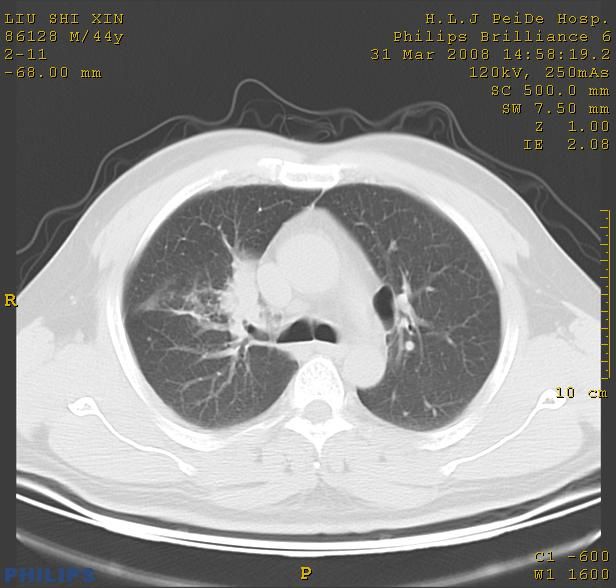

标题: CT13096:请分析胸膜下结节的影像基础是什么 有病理结果 [打印本页]

标题: CT13096:请分析胸膜下结节的影像基础是什么 有病理结果

考虑右上叶慢性炎症可能性大,不完全除外肺癌。

瘢痕挛缩,胸膜牵拉,血管纠集扭曲,上叶前段支气管显示欠清,周围散在斑片影,以纵隔旁肺癌可能性大。请穿刺检查。

中心型肺癌并阻塞性肺炎及肺内转移

中心型肺癌并阻塞性肺炎、两肺及胸膜多发转移。

结节灶与血管末梢相通象转移灶;小三角状尖部有纤维索是胸膜拉扯征;纵隔旁大片实性影有点状钙化;周围有名显纤维瘢痕征可考虑瘢痕癌

本病例有病理结果是,鳞状上皮癌,胸膜下结节影病现诊断的肿大淋巴结,谢谢大家分析,请问胸膜下结节是肿大淋巴结怎么解释